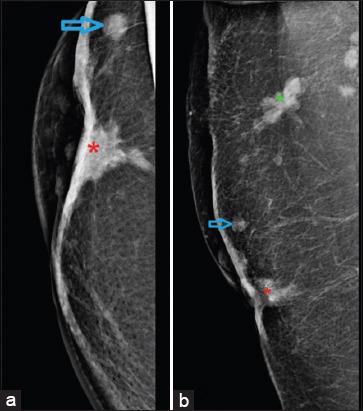

A total of eight cases were identified, out of which seven were females. The most common presentation consisted of the presence of metastatic nodules which were seen in 62.5% (five out of eight) of the patients. Other features consisted of erythematous or plaque-like skin thickening on clinical examination, increased density with indistinct margins seen on a mammogram and diffuse oedematous changes in the skin with small irregular mass or infiltration into subcutaneous tissues were visualised on ultrasound and CT studies.

Skin metastasis from breast cancer most commonly presents as nodules, although rarely they may present as plaques or diffuse skin thickening. Awareness of diverse manifestations of skin metastasis is of utmost importance in early diagnosis and management.